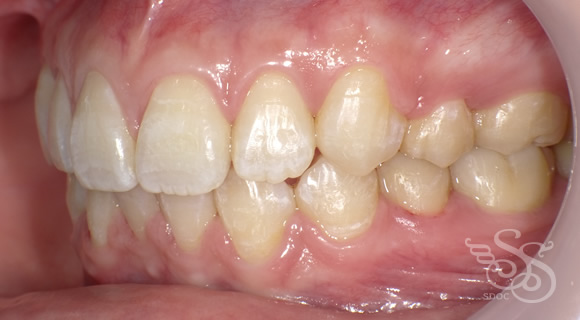

右側:術前

右側:術後